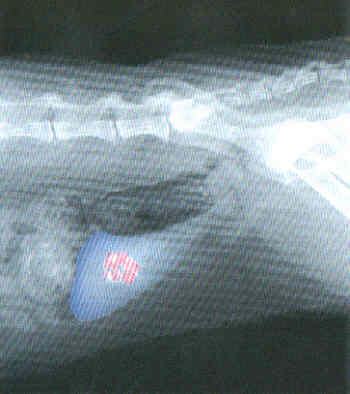

Blasensteine, Röntgenbild

Die meisten Blasensteine können durch eine Röntgenaufnahme entdeckt werden. Für die weitere Behandlung ist eine genaue Analyse der Blasensteine erforderlich.